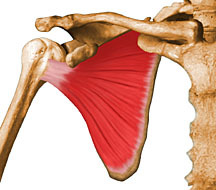

DIGA O NOME DESTE MÚSCULO

MÚSCULO DELTÓIDE